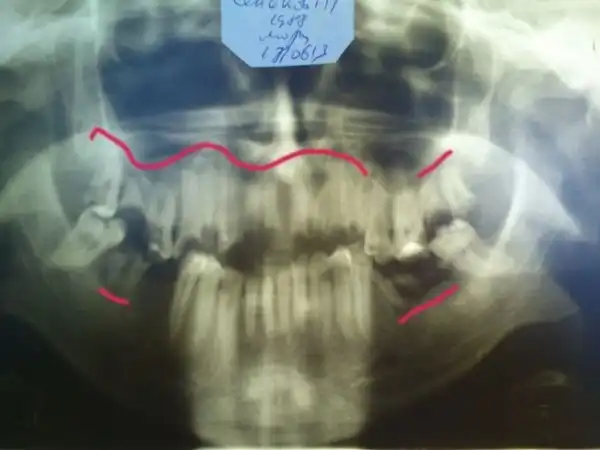

Угадайте, а сколько лет этому пациенту? По понятным причинам я не фотографировал его лицо полностью… Изначально он обращался около двух месяцев назад с переломом нижней челюсти в области суставного отростка слева, и шины наложить ему не могли, т.к. зубов целых почти нет… Был направлен в областную больницу, где походил с пращевидной бинтовой повязкой, и был отпущен домой… Остеосинтеза никто ему не делал. А потом спустя месяца два попал ко мне, после того как у себя на работе упал и ударился тем же местом)))) Очень «правдоподобно»… Но не в этом суть, парню 25 лет!!! Считает, что зубы разрушены, т.к. он на вредном производстве на заводе работает. Но гораздо более вероятная причина — нежелание чистить зубы. На фотографии видно, сколько там налета. И так многие выдумывают самые невероятные причины: работа с кислотой, жизнь в тайге, дальние плаванья, утрата зубов за один месяц после родов и т.п. Все это может повлиять в какой-то степени, но на деле у всех этих пациентов ужасная гигиена и последнее посещение стоматолога при царе Грохе. А у нашего парня зато татуха на всю правую руку, и на то, чтоб ее сделать, он нашел и время, и деньги, и желание… Это наш менталитет… Ездить на дорогой машине, понаделать татух, пирсинг, ходить в дорогих шмотках, но при этом с грязными ушами и нечищеными зубами. Редко кто на приеме попадается с таким уровнем гигиены, чтоб можно было стоматологическое вмешательство проводить. Да-да, есть индекс гигиены специальный, и если он выше определенной величины, то удалять нельзя. Но на деле удаляю, т.к. если строго подходить, то принять можно будет 2-3 человек за смену, остальных отправлять чистить зубы… Но потом люди приходят и с удивлением спрашивают, почему лунка после удаления болит? Никому даже в голову не приходит, что одной из вероятных причин может быть помойка во рту… Так что, друзья, идете к стоматологу — почистите зубы хорошенько ( да и вообще их чистить надо)), даже этой мелочью вы обеспечите себе хорошее отношение врача, потому что чистый рот — большая редкость и приятная неожиданность для стоматолога( к сожалению).

А это его панорамная рентгенограмма. То, что обвел красным, надо удалять. В 25 лет этому парню надо ставить съемные пластиночные протезы. Это такие, как вы видели у своих бабушек и дедушек в стаканах на тумбочке у кровати…

Еще пару слов о гигиене… Вот два типичных пациента. У одного укроп на зубах, у второго камни (видны в зеркале). И это не самые яркие примеры. Представьте, что после удаления попадает в кровоточащую лунку… Меня вообще трудно удивить или вызвать отвращение, но некоторым удается. Иногда просто отправляю из кресла идти чистить зубы. Где? Меня не касается… Так обижаются!!! Тонкие натуры) Был случай, как одного такого запущенного принял, удалил зуб, но предупредил, что если еще раз с таким ртом придет, то я его не приму. Он пришел- картина та же. я ему в приеме отказал. Это первая смена была. А вечером зашел в кабинет зачем-то, там мой коллега прием вел, смотрю -сидит у него в кресле мой утренний пациент. Спрашиваю доктора, почистил ли тот мужик зубы, а он мне говорит, что такой помойки он не видел еще, как у него во рту… Занавес…